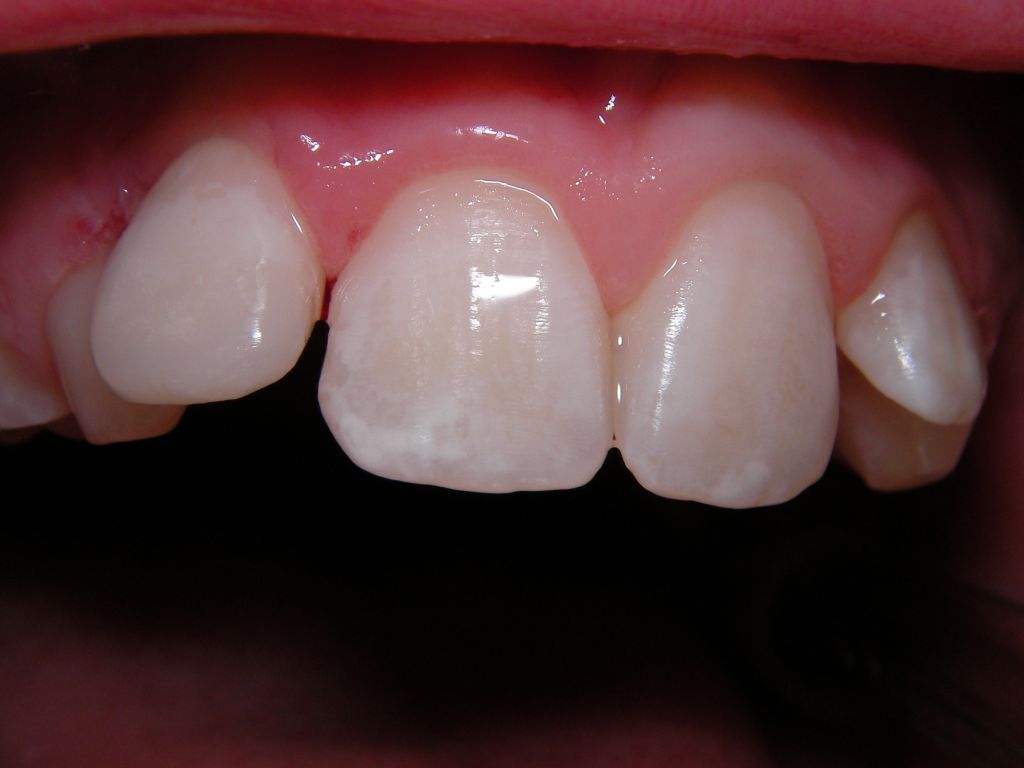

![]() | Das Kind kam nach dem Unfall in die Praxis. Der Zahn war heiß-/kaltempfindlich und wurde erst einmal über ein paar Wochen mit einem provisorischen Zement versorgt. Die Beschwerden klangen ab, dann erfolgte die endgültige Füllung (ohne Zuzahlung), siehe rechts. Eine langfristige Alternative wäre hier eine keramische Verblendschale (Veneer), aber dafür ist das Kind aktuell zu jung. |

![]() | |||||||||||||||||||||||||||||||||||||||||||||||||||||||||||||||||||||||